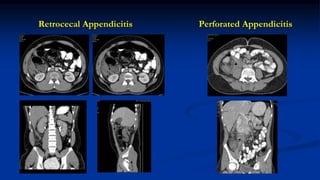

Retrocecal Appendicitis Perforated Appendicitis

Right Lower Quadrant Pain

 Common presenting symptom

 Ac appendicitis, IC Tb, IBD, amoebic typhlitis, mesenteric adenitis, adnexal

pathology

 Omental infarction, epiploic appendagitis, neutropenic enterocolitis

 Central abdominal pain which shifts to RIF, leucocytosis

 USG followed by CT is the way to go

 Reported sensitivity & specificity of CT for appendicitis: 90-99%